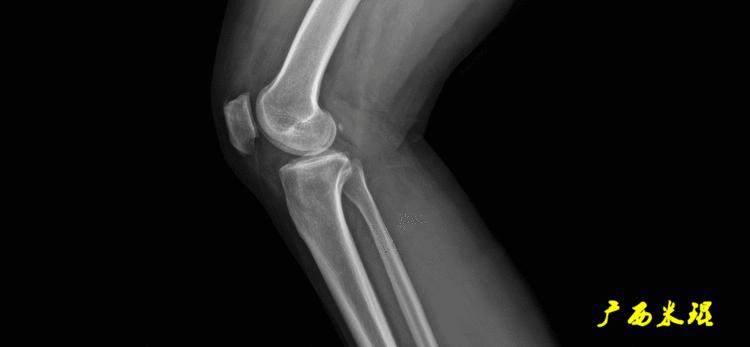

股骨远端外侧角(mLDFA):股骨内外侧髁远端切线(关节线)与股骨头和膝关节中心的连线(机械轴)两者之间形成的外侧夹角,正常为87°±3°。

解剖股胫角(aFTA):股骨干下段轴线(解剖轴)与胫骨上段轴线(解剖轴)在膝关节所形成的夹角,正常为174°±1°。膝关节OA的畸形常常由于一侧软组织及关节的过度磨损所致,临床多为内侧磨损过度,因此表现为轻度膝内翻畸形,X线表现为解剖股胫角小于174°,而胫骨角正常。

解剖股骨远端外侧角(aLDFA):股骨干下段轴线(解剖轴)与股骨内外侧髁远端切线(关节线)在膝关节外侧所形成的夹角,正常为81°±2°。大多数膝外翻患者的畸形发生于股骨下端,表现为股骨远端外侧角小于正常值。

胫骨股骨关节线夹角(JLCA):胫骨近端关节线与股骨远端关节线之间的夹角,正常生理状态下几乎为0°。当JLCA>2°时提示异常,通常为韧带松弛或者软度磨损丢失所致。